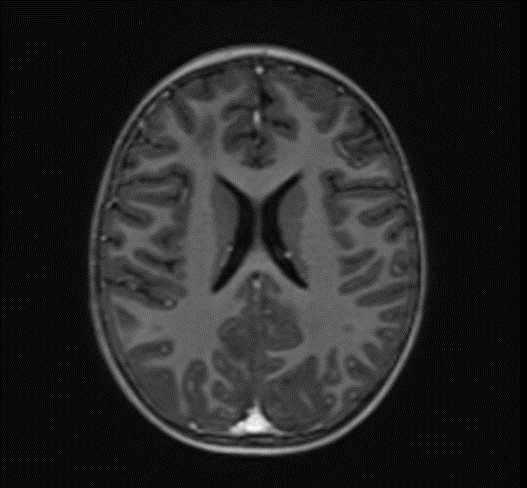

Subsequently, an MRI of the brain was performed, which demonstrated: Bilateral diffuse high signal changes in the cerebellum on T2 and FLAIR sequences, as well as areas of restricted diffusion, indicating focal zones of cytotoxic edema.

Picture 2.

The MRI of the brain revealed the following findings:

- Bilateral subcortical zones, predominantly in the occipital region, exhibiting confluent hyperintense signals on T2 and FLAIR sequences, accompanied by edema.

- A suspected area of cytotoxic edema in the superior parietal lobe.

- High signal intensities on T2 and FLAIR sequences observed in the centrum semiovale, right of the corpus callosum body, and bilaterally in the frontal gyrus, without diffusion restriction.

- In the supraventricular region, extending inferiorly from the projection of the postcentral gyrus into the subcortical white matter to the posterior part of the corpus callosum body (excluding it), and in the left superior temporal lobe, there was a cortico-subcortical lesion characterized by cytotoxic edema and restricted diffusion.

The changes observed are characteristic radiological markers appreciated on DWI, indicative of cytotoxic edema. The DWI changes are considered reliable early signs of acute toxic encephalopathy, specifically methotrexate-related leukoencephalopathy. Post-contrast MR images did not show any abnormal contrast enhancement.

Bilateral Occipital Dominant Subcortical Hyperintense Zones: These areas were evident on T2-weighted and FLAIR sequences, indicating diffuse cerebral involvement. The predilection for the occipital region was consistent with reported cases of MTX-LE, which often presents with symmetric white matter changes.

Edema and Cytotoxic Edema: The superior parietal lobes showed suspected zones of cytotoxic edema. This was further supported by the presence of diffusion-weighted imaging (DWI) changes, characterized by restricted diffusion, a hallmark of cytotoxic edema. These findings align with the pathophysiology of MTX-LE, where MTX-induced neuronal damage leads to cellular swelling and subsequent restricted diffusion.

Supraventricular and Frontal Gyrus Involvement: High signal intensities on T2 and FLAIR sequences were noted in the centrum semiovale, right of the corpus callosum body, and bilaterally in the frontal gyrus, without diffusion restriction. This suggests early involvement before the development of significant cytotoxic damage.

Cortico-Subcortical Lesion in the Left Superior Temporal Lobe: This region exhibited cytotoxic edema with restricted diffusion, underscoring the multifocal nature of MTX-LE. The involvement of both cortical and subcortical areas is a typical feature in severe cases of MTX-LE.